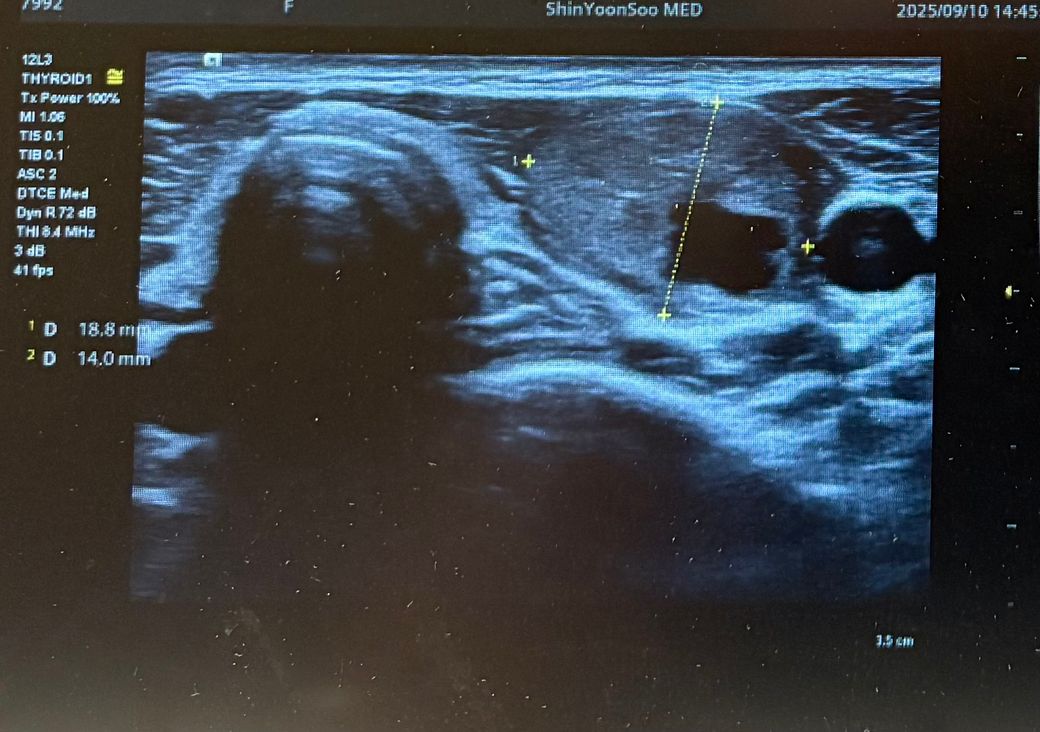

최근 동네 의원에서 갑상선초음파를 보다가 왼쪽 갑상선에 큰 혹 한개와 작은혹 한개가 발견되어 조직검사가 필요할것 같다고 의뢰서를 써주셔서 상급병원으로 예약잡고 저번주에 초진 봤습니다.

Lt 1ower lobe

1.88x1.4x2.84cm mixed nodule Lt middle lobe 1.22x0.37x 0. 49cm의 nodule 소견으로(의뢰서에 적혀있던 내용) 초진 보러가니 초음파 사진만 보시고는 식도와 신경에 들러붙어있고 점점점 커지면서 추후엔 응급수술로 진행될 수 있으니 아직 젊을때 빠르게 수술로 떼어내자고 결론은 수술밖에 없다고 냅다 수술일정 한달뒤로 잡고왔습니다.

왼쪽에 약 3cm가량으로 전체가 혹일거라며 상황이 많이 안좋은거고 위치가 안좋다고 하셔서 다음주에 수술전 검사 받은 후 2주뒤 입원으로 일정이 잡혔는데 보통 세침검사 또는 총생검사 후 수술 여부가 결정되는걸로 알고있는데 ..

• 1번 째 사진